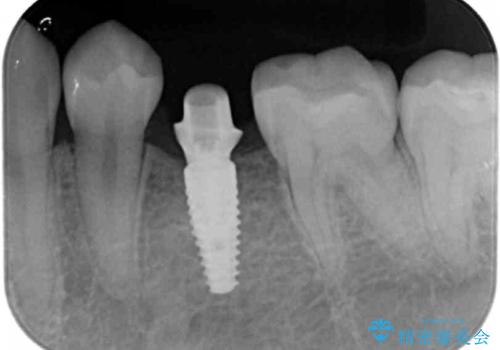

通常矯正治療は後戻りがあるので保定が必要です。

しかし、今回は不要でした。

矯正治療で歯を移動して得られたすき間はインプラントのクラウンで動かないようにできるためです。

保定が不要という点におきましては、部分矯正と補綴(被せ物)治療は非常に相性がよく、得られるメリットも大きいといえます。